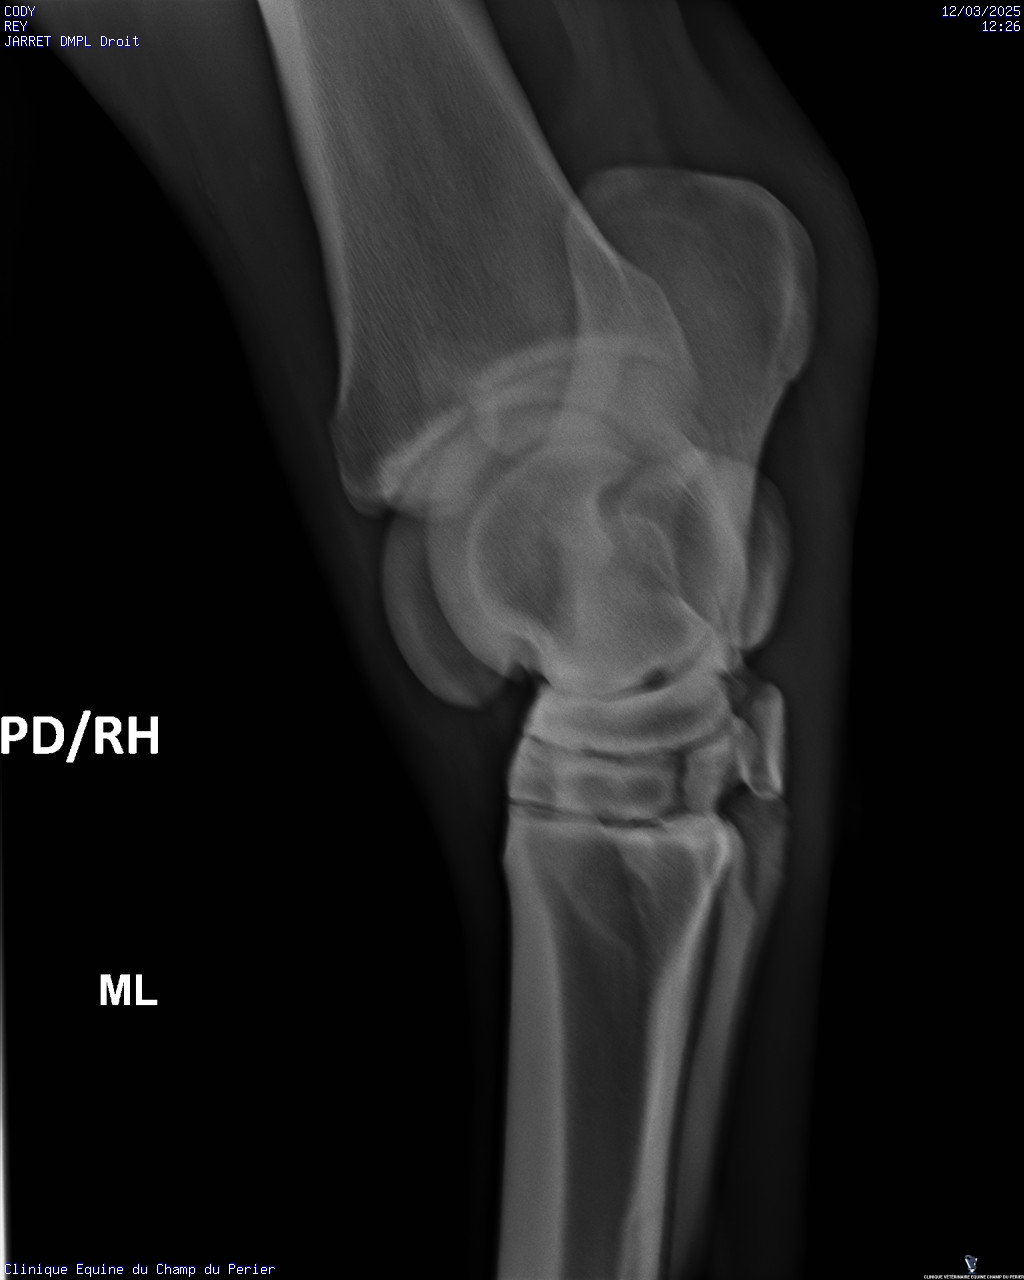

| Dire merci | Voici les résultats : - pieds antérieurs : novembre 2024 : perte de parallélisme entre les 3° phalanges des deux antérieurs et les sabots-parois dorsales ; pieds trop longs en pinces - pieds postérieurs ce jour : très léger défaut de parallélisme entre P3 et parois dorsales des sabots, mais pinces trop longues. Un défaut en phase de correction sou le sabot PG, en ponte de fourchette. On note aussi un ostéophyte au sommet dorsal de P2 sur le PD. - jarrets : on note sclérose des os centraux et troisièmes os des tarses + lyse forte de ces deux os sur le jarret gauche Ccl : comme indiqué sur mon ordonnance il faut : - parer les sabots afin d’obtenir au fur et à mesure le parallélisme entre les 3° phalange et les parois dorsales des sabots ; parer les pinces des sabots au plus court - poser des fers qui seront bien reculés et donneront de la surface d’appui en talons, sur les deux antérieurs - soulager la douleur pour les deux mois à venir avec Equioxx° un comprimé par jour. Le contrôle des enzymes rénales – normales – fait se jour le permet. - traiter CODY avec des biphosphonates (Osphos°, voire Tildren°) |

| Dire merci | C'est quoi une forte lyse ? C'est ça qui lui avait fait gonflé le jarret ? Finalement pas de fourbure ? (Tant mieux) (Et pour les anomalies que tu avais entouré en bleu sur les anciennes radio ? Il a dit quelque chose de spécial ?) |

| Dire merci | C'est pas une perte d os un peu comme l'osteoporose? Et donc un.machin lié à arthrose? Un veto pour expliquer? Message édité le 12/03/25 à 21:18 |

| Dire merci | Oui l’ostéolyse c’est la destruction du tissu osseux. Mais il n’avait jamais eu de radios du jarret G dans les multiples examens déjà faits? Parce que c’est vraiment pas beau là ![]() |

| Dire merci | Mais il n’avait jamais eu de radios du jarret G dans les multiples examens déjà faits? Parce que c’est vraiment pas beau là Je suis d'accord avec toi Juliie . Je ne voulais pas intervenir directement après le post des radios pour ne pas être la rabat-joie. Mais c'est pas job job au niveau des articulations (toutes les articulations en fait). Enfin le véto a dû te le dire. Quand ils préconisent du Tildren c'est que c'est déjà sérieux et bien avancé (en gros, le Tildren essaye de "bloquer" l'articulation en l'état pour ne pas que ça se dégrade davantage et je crois qu'il a aussi une action antalgique). Il a quel âge ton cheval ? Message édité le 12/03/25 à 23:45 Message édité le 12/03/25 à 23:45 |

| Dire merci | L'état du jarret gauche n'est pas bon. Il n'y a jamais eu de radios de faites, les différents pros m'ont dit que c'était sa conformation. J'ai dû insister pour faire les radios. Avec mon véto habituel on va programmer un tildren assez rapidement. Cody va prendre 11 ans cette année. De ce que j'ai compris les antérieurs douloureux font qu'il y a un report du poids sur les postérieurs. La priorité est de soulager la sensibilité des antérieurs, pas de chance le maréchal-ferrant s'est trompé de taille de fers, le ferrage est reporté de 10 jours. En attendant je dois donner un cachet d'equiox par jour. |